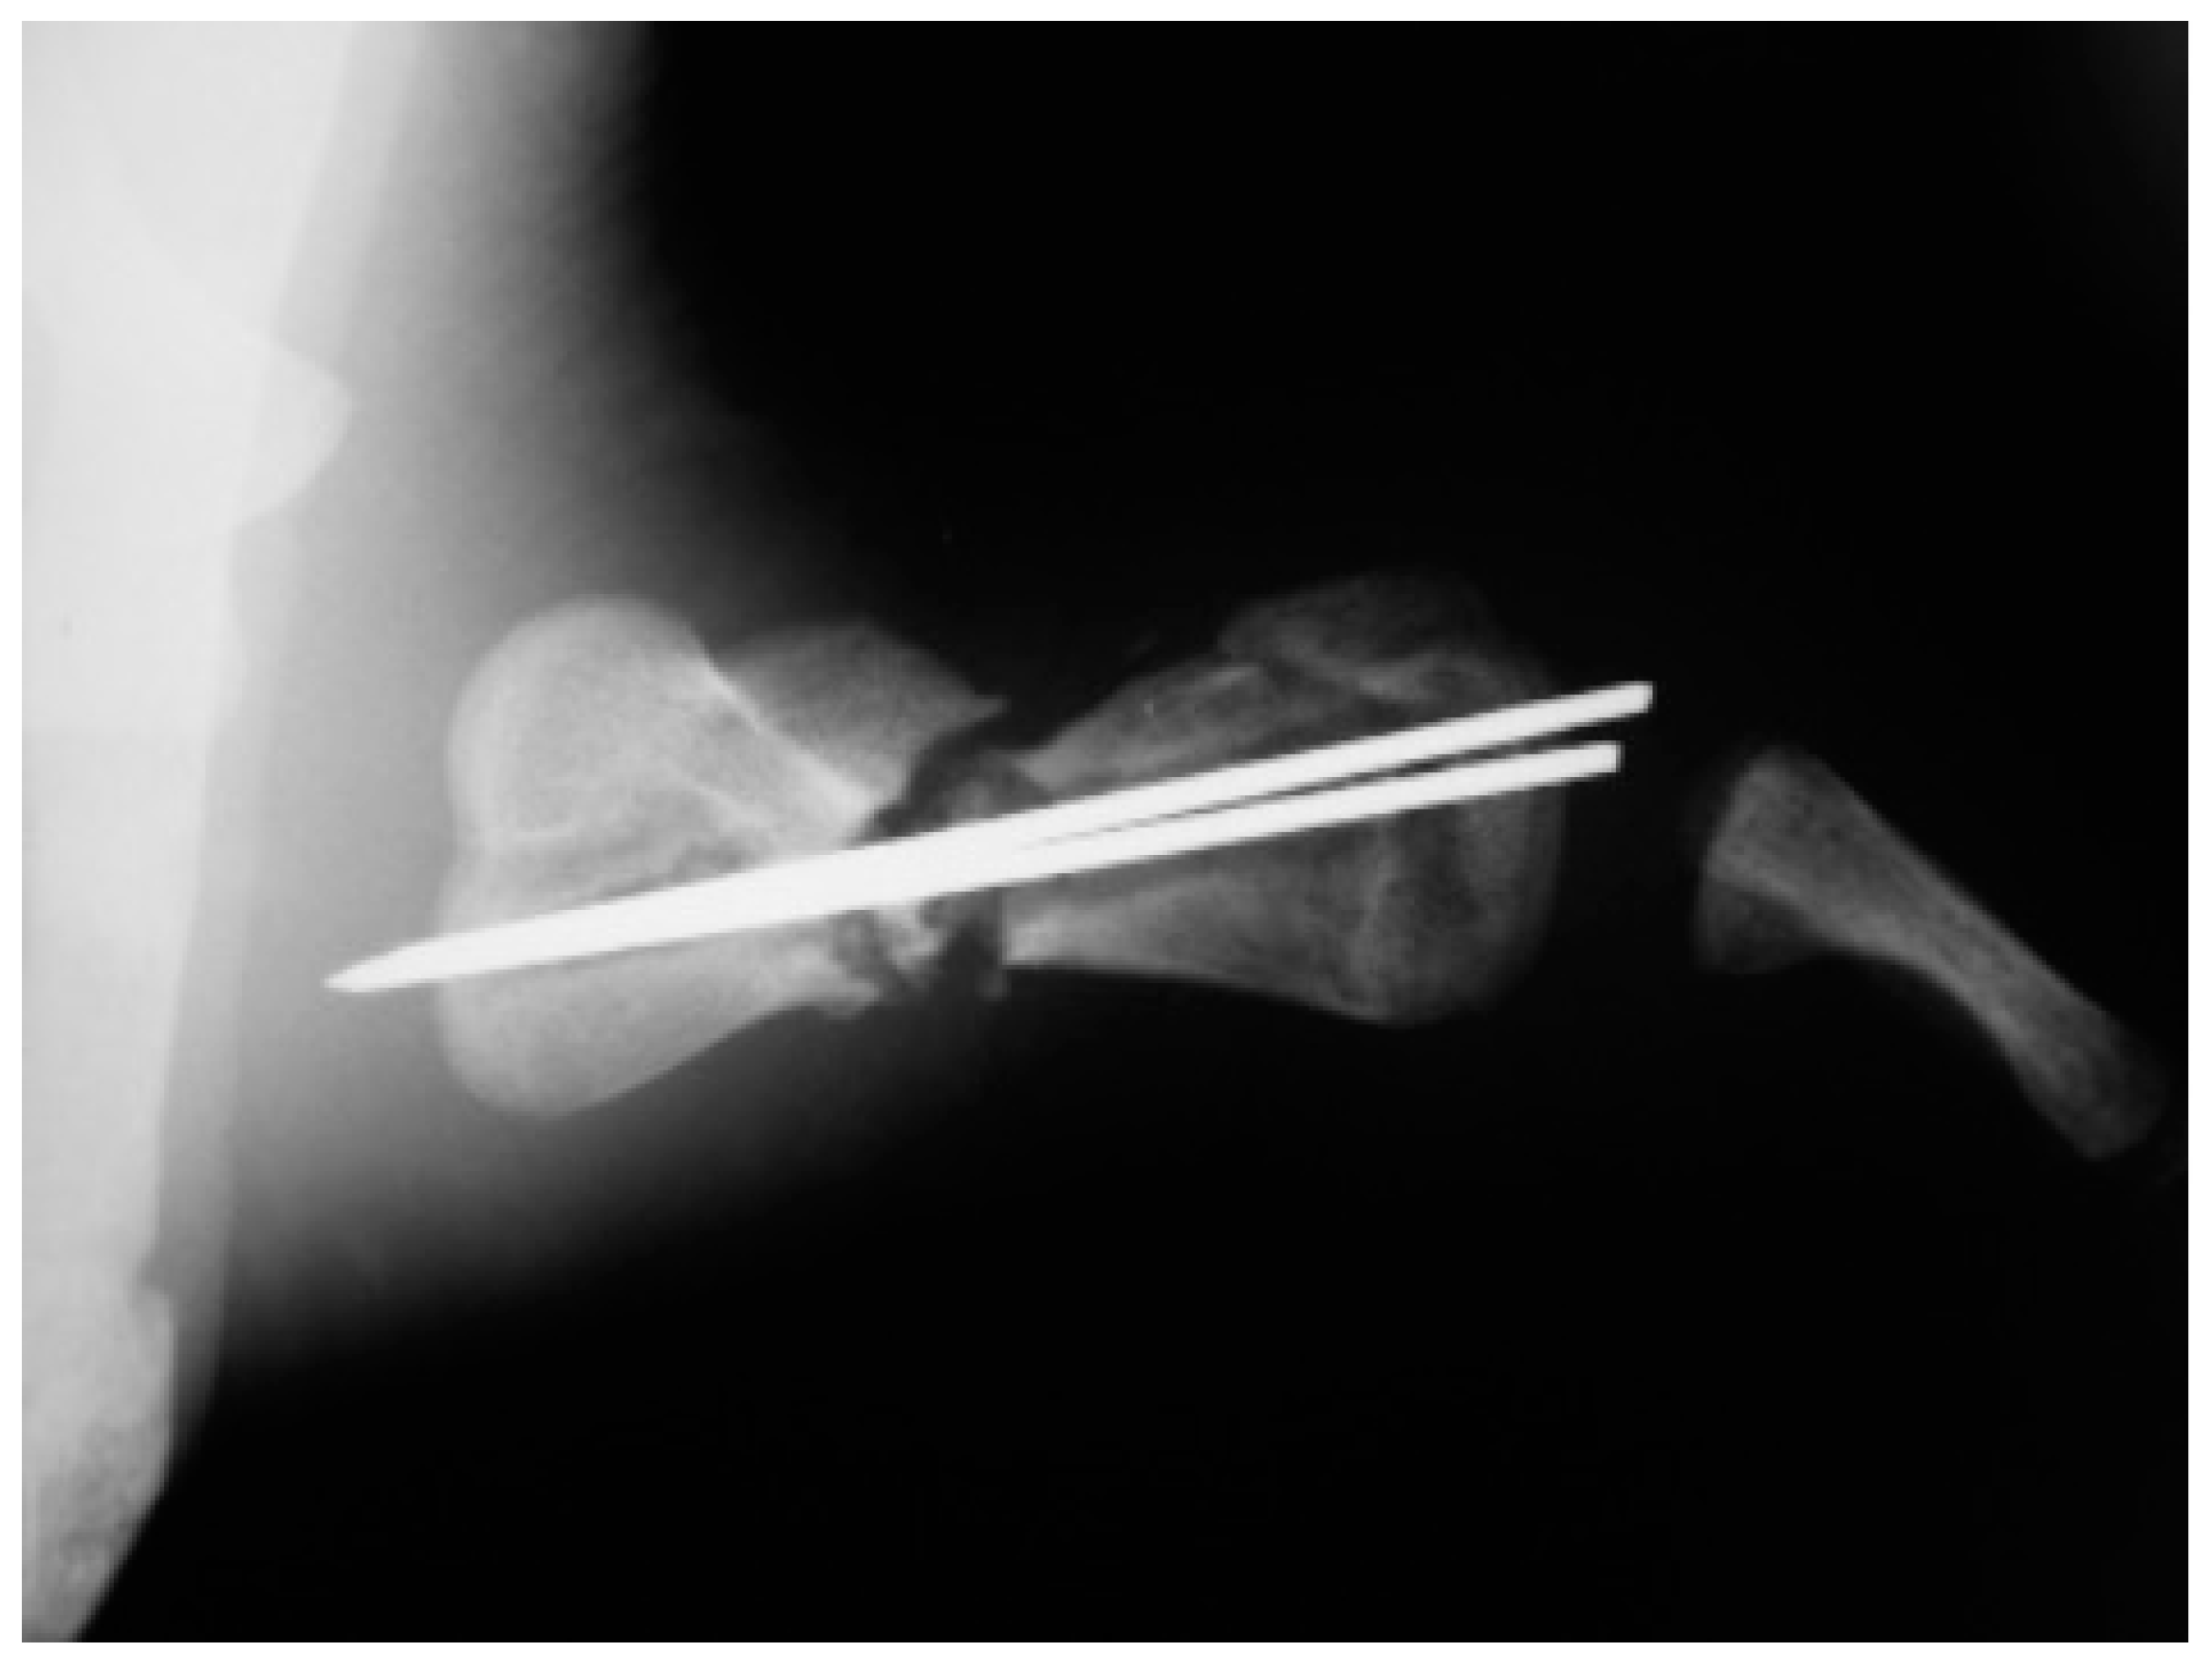

A juvenile sea turtle was presented to the Sea Turtle Clinic (STC) of Veterinary Medicine Department of the University of Bari with an entanglement lesion affecting the right front flipper. On admission, the sea turtle was measured and underwent a complete physical examination; curved carapace length (CCL) from notch to tip ranged 41 cm, curved carapace width (CCW) was 37 cm, and the weight was 18 Kg. The turtle appeared responsive but weak and dehydrated. Clinical evaluation of the musculoskeletal system performed out of the water showed swelling of the right front flipper and evidence of pain on deep palpation of the respective brachial muscle. A reduction in the right front flipper’s range of motion was observed when the turtle was examined in the water. Radiographic assessment, in dorso-ventral (D-V) and Caudo-Cranial (C-C) projections, indicated detachment of the distal epiphysis of the humerus, compatible with a type II Salter-Harris fracture, together with a transverse diaphyseal fracture (Figure 1). The turtle underwent general anesthesia, and the craniodorsal access to the humeral diaphysis was performed. The epiphyseal fracture was reduced by closed surgery and fixed using two crossed 2.5 mm Kirschner pins, introduced backward from the distal stump and brought out through the hyperflexed humerus-radio-ulnar joint. The same pins used to fix the epiphyseal fracture were inserted into the proximal stump to fix the diaphyseal fracture. After checking the stability of the fractures reductions, the surgically sectioned soft tissues were reconstructed, and post-operative radiographs were performed. Follow-up was performed after the surgery at 2, 4, 12, 16, and 24 months, when the turtle was released at sea. Three months after its release at sea, the turtle was caught dead in a fishing net at a depth of 40 m. To determine the evolution of bone repair from turtle release to death, the right humerus was removed for histological and histomorphometry analyses. Immediately after explant, the humerus was fixed in 4% buffered paraformaldehyde, dehydrated in ethanol, and embedded in methylmetacrylate. Serial cross sections, 750 µm thick, were cut at both the diaphyseal and epiphyseal fracture gaps using a circular diamond-bladed saw (Gillings Hamco) and were ground to a thickness of 100 µm. Sections were placed on a specimen holder and microradiographed using a microradiograph (Constant 1-K, Ital Structures, Italy) at a prefixed distance from the X- ray generator of 9.5 cm. X-ray exposure was set up at 8 kV and 14 mA. Contact microradiographs were obtained on Kodak high-resolution film (SO 343, Eastman Kodak Co., Rochester, NY, USA), developed with Kodak HC-110, fixed in Kodak UNIFIX, washed in distilled water and then airdried at room temperature. Sections were subsequently stained with 1% toluidine blue (pH 3.7) for mineralized tissue. Four separate levels were selected, three belonging to the mid-diaphyseal fracture gap, and one level to the epiphyseal fracture gap: the first and the fourth levels corresponded to the proximal and distal part of the callus, respectively, and the second and third levels to the center of the fracture (Figure 2). As a control, the left humerus, which had never been fractured, was processed with the same procedure. On the stained sections, using a Nikon DS-5 camera connected to a stereomicroscope (SMZ800, Nikon Europe B.V., Amstelveen, The Netherlands) and a DS camera control unit, the callus extension was measured and the amount of new laid down bone, cartilage, and fibrous tissue, expressed as percentage ratio of the entire section, were evaluated. Histomorphometry was performed using Nis-Elements BR analysis software (Nikon Europe B.V.).

Figure 2. X-ray image of the humerus showing the levels from which the histological and morphometric findings and the microradiographs. Numbers 1 to 4 correspond to the first, second, third and fourth diaphyseal level, respectively. Number 5 corresponds to the distal epiphysis level.